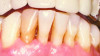

Fig 4. Case 1. Initial presentation of a patient with periodontitis (teeth Nos. 22 through 27). Generalized pocket depths of 5 mm to 6 mm were present.

Figure 4

Fig 6. Results of SRP demonstrated resolution of inflammation and residual probing depths of 2 mm to 3 mm, 18 years after treatment of Case 1 patient.

Figure 6